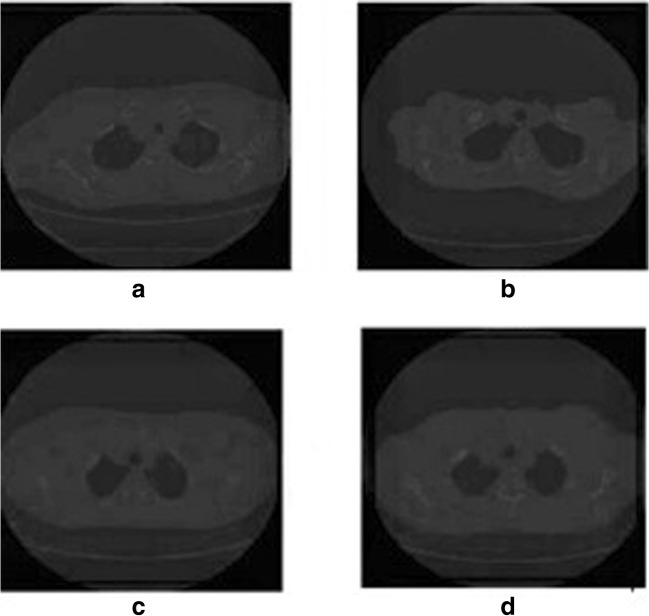

Fig. 4.

CT images of patients with emphysema condition as a minimal or no emphysema, b centrilobular emphysema, c paraseptal emphysema, and d pan-lobular emphysema